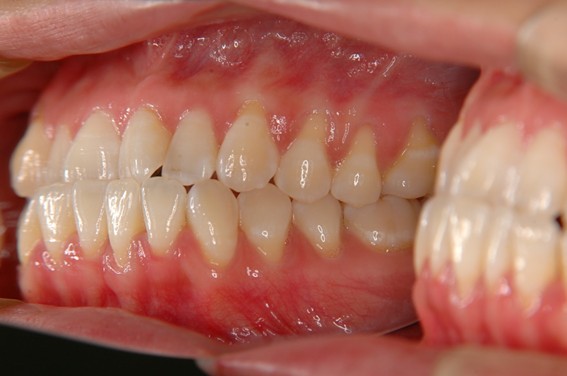

| 主訴 | 前歯が逆に噛んでいる。 |

| 治療内容 | 表側ワイヤー矯正、ジルコニア補綴を行いました。 |

| 治療費 | ワイヤー矯正660,000円(税込) ジルコニア176,000円(88,000円×2歯)(税込) |

骨格性Ⅲ級・前歯部反対咬合の症例でした。反対咬合のまま治療していた前歯のサイズ不調和を、表側ワイヤー矯正とプロビジョナルクラウンで調整。正中を整え、犬歯・臼歯ともⅠ級、適切なオーバージェット(上下前歯の前後的な距離)・オーバーバイト(上下前歯の垂直的な重なり)に仕上げました。